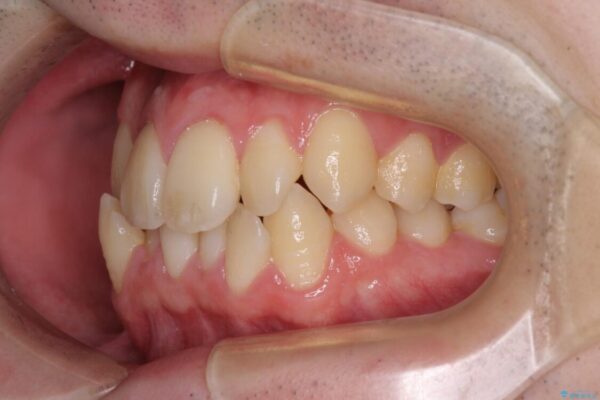

治療途中

• 全顎的なクロスバイト 補助装置を用いてワイヤー矯正 治療途中画像